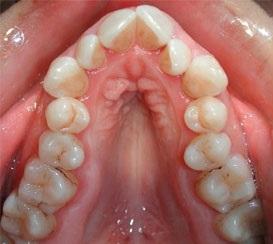

Deformación del paladar: debido a la fuerza que ejerce el dedo hacia arriba durante la succión del dedo el paladar modifica su forma haciéndose cada vez mas convexo, mas estrecho. A esta deformación la llamamos paladar ojival.

paladar ojival

Paladar ojival.